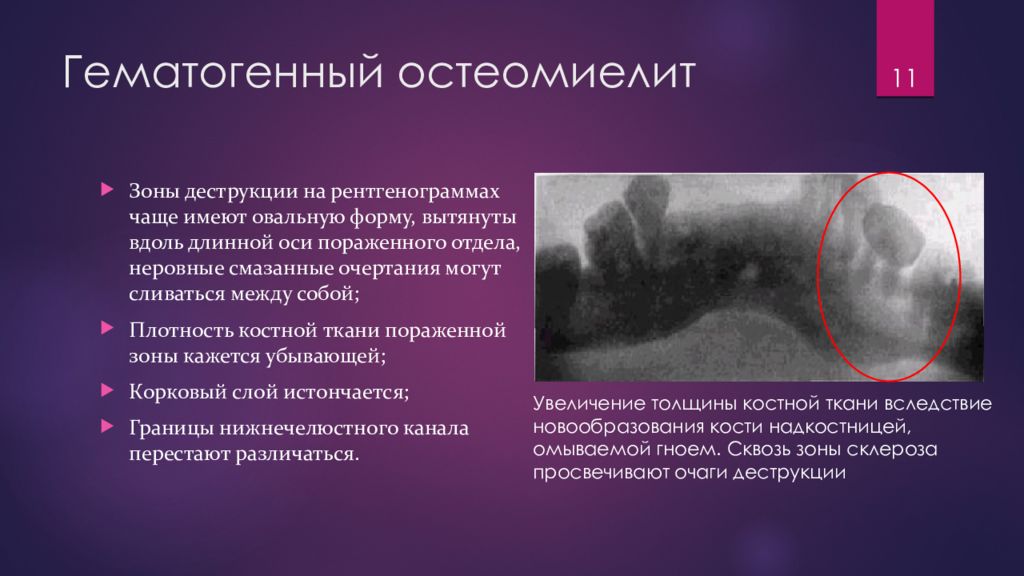

Рентгеновские снимки посттравматического остеомиелита челюсти: Медицинские случаи

Раздел: Образы вокруг